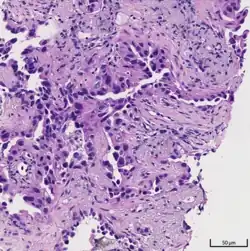

Histopathology

If possible, a biopsy of any suspected lung tumor is performed to make a microscopic evaluation of the cells involved and is ultimately required to confirm diagnosis.[7] Biopsy should be attempted in distant lesions first to establish a histologic diagnosis and to simultaneously confirm metastatic staging. The biopsy material is also used to analyze whether the tumor express any specific mutations suitable for targeted therapy (e.g. EGFR mutation or ALK mutation). Biopsy can be accomplished via bronchoscopy, transthoracic needle biopsy, and video-assisted thorascopic surgery (VATS).[4]

Adenocarcinoma of the lung tends to stain mucin positive as it is derived from the mucus-producing glands of the lungs. Similar to other adenocarcinoma, if this tumor is well differentiated (low grade) it will resemble the normal glandular structure. Poorly differentiated adenocarcinoma will not resemble the normal glands (high grade) and will be detected by seeing that they stain positive for mucin (which the glands produce). Adenocarcinoma can also be distinguished by staining for TTF-1, a cell marker for adenocarcinoma.[29]

As discussed previously, the category of adenocarcinoma includes are range of subtypes, and any one tumor tends to be heterogeneous in composition. Several major subtypes are currently recognized by the World Health Organization (WHO)[1] and the International Association for the Study of Lung Cancer (IASLC) / American Thoracic Society (ATS) / European Respiratory Society (ERS):[30][31][32] lepidic predominant adenocarcinoma, acinar predominant adenocarcinoma, papillary predominant adenocarcinoma, micropapillary predominant adenocarcinoma, solid predominant adenocarcinoma, and solid predominant with mucin production. In as many as 80% of these tumors, components of more than one subtype will be recognized. Surgically resected tumors should be classified by comprehensive histological subtyping, describing patterns of involvement in increments of 5%. The predominant histologic subtype is then used to classify the tumor overall.[2] The predominant subtype is prognostic for survival after complete resection.[33]

To reveal the adenocarcinomatous lineage of the solid variant, demonstration of intracellular mucin production may be performed. Foci of squamous metaplasia and dysplasia may be present in the epithelium proximal to adenocarcinomas, but these are not the precursor lesions for this tumor. Rather, the precursor of peripheral adenocarcinomas has been termed atypical adenomatous hyperplasia (AAH).[10] Microscopically, AAH is a well-demarcated focus of epithelial proliferation, containing cuboidal to low-columnar cells resembling club cells or type II pneumocytes.[10] These demonstrate various degrees of cytologic atypia, including hyperchromasia, pleomorphism, prominent nucleoli.[10] However, the atypia is not to the extent as seen in frank adenocarcinomas.[10] Lesions of AAH are monoclonal, and they share many of the molecular aberrations (like KRAS mutations) that are associated with adenocarcinomas.[10]